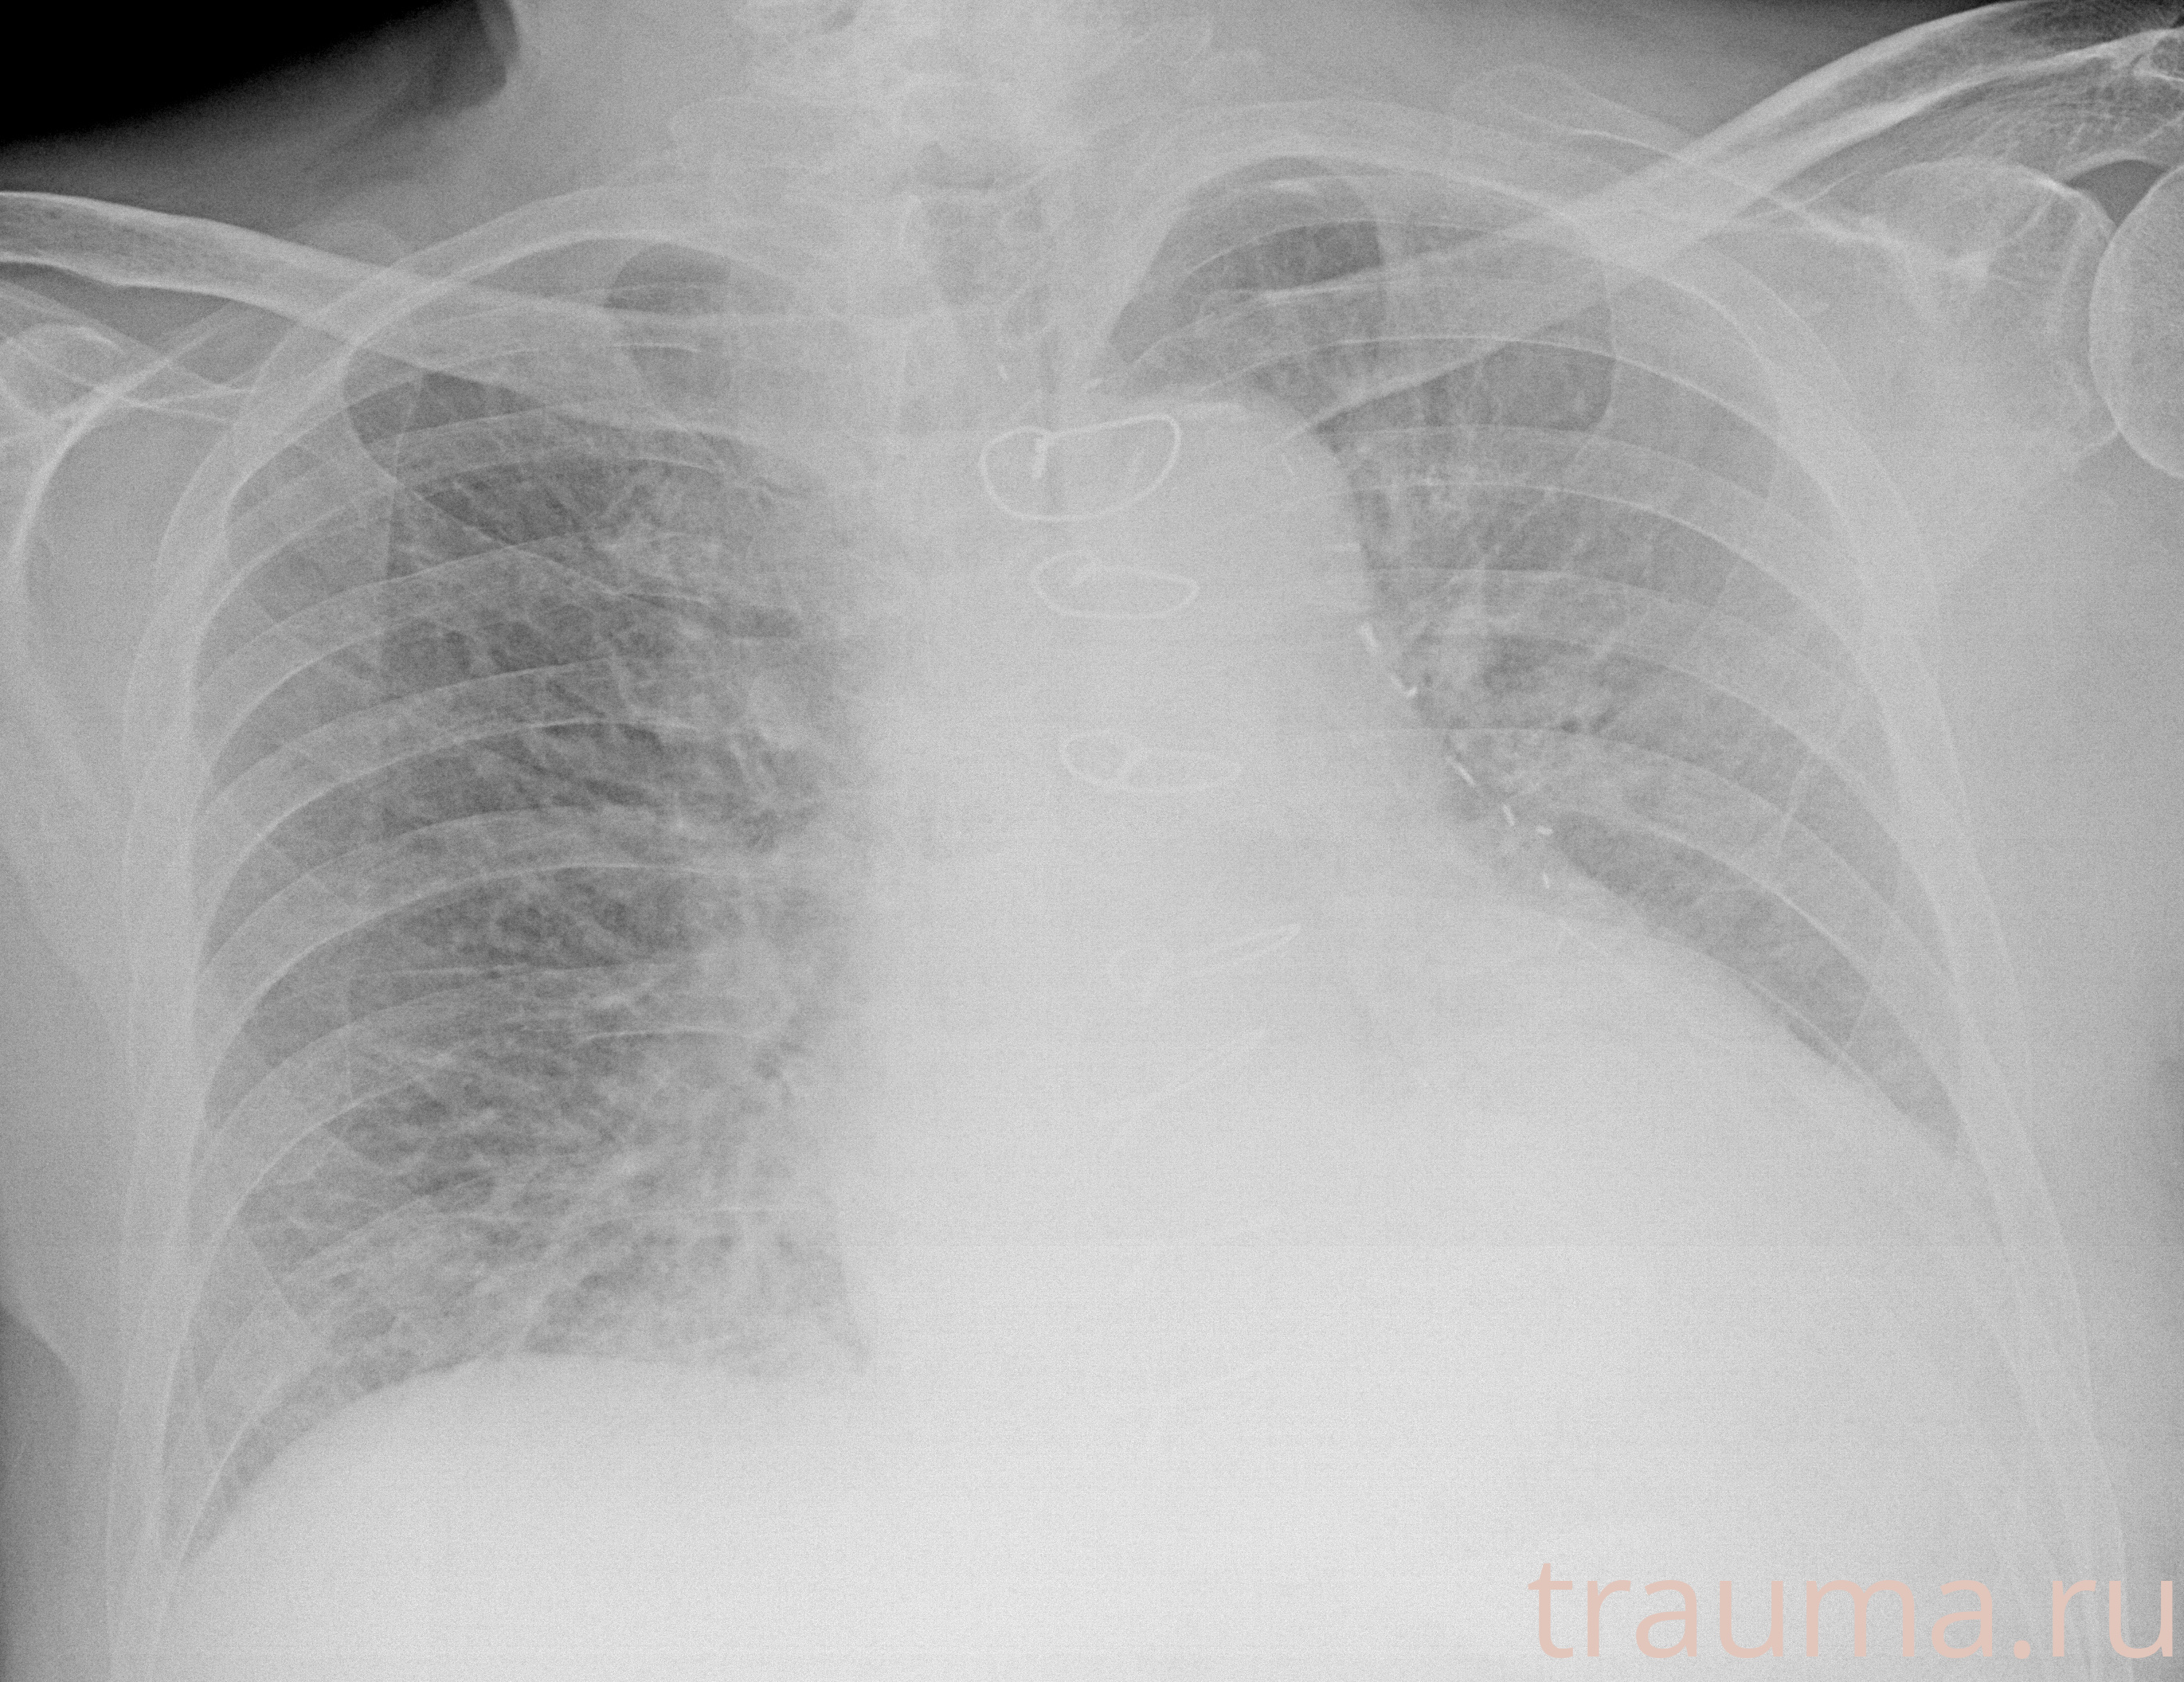

Рентгенограммы

Рентген на дому: по вашему адресу приезжает врач-рентгенолог, травматолог-ортопед с мобильным рентгеновским аппаратом, проводит диагностику травмы или заболевания, делает необходимые рентгенограммы, дает рекомендации по дальнейшему лечению. Получить качественные снимки в домашних условиях возможно благодаря уникальной методике, разработанной МосРентген Центром для института  Склифосовского

Яркость: 1   Контраст: 1   Инвертировать: 0 Увеличение: 1

Перетаскивайте мышь вверх/вниз для контраста, влево/право для яркости. Прокрутка колесом изменяет масштаб. Нажмите Сбросить для возврата к исходному изображению. При увеличении держите мышь в той области, которую хотите рассмотреть.